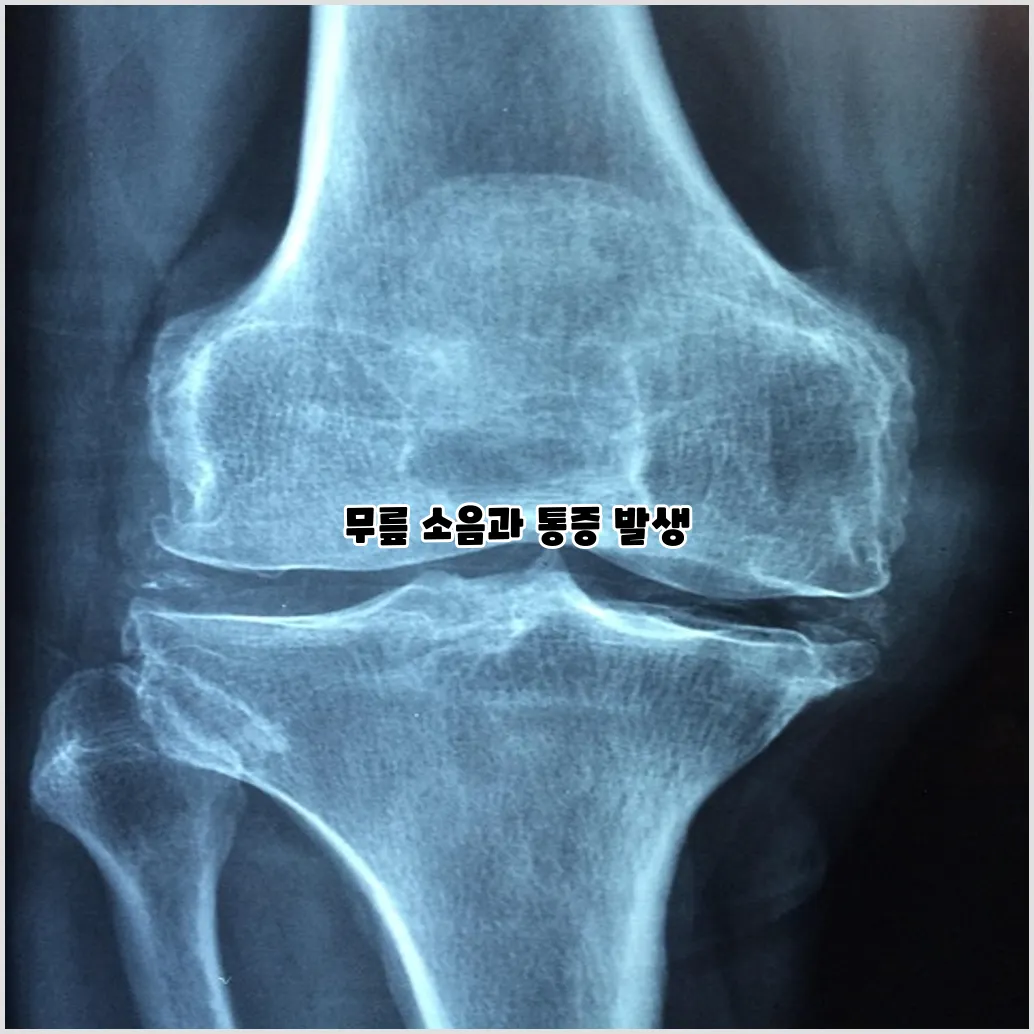

소리 및 크랙음

운동 도중 무릎에서 소리나 크랙음이 나는 경우도 흔한 증상이 될 수 있습니다. 이는 연골의 손상으로 인해 관절 내에서 비정상적인 마찰이 발생하기 때문입니다. 이 소음은 특별히 통증을 동반하지 않을 수도 있지만, 무릎의 상태가 좋지 않다는 신호일 수 있습니다.

무릎에서 소리가 나는 것은 무릎 연골 손상의 신호인가요?

네, 무릎에서 소리가 나는 것은 무릎 연골 손상의 신호일 수 있습니다. 이러한 소리는 일반적으로 관절이 정상적으로 움직이지 않을 때 발생하며, 마찰이나 잡음이 생길 수 있습니다. 이는 연골의 손상이 있을 때 나타나는 일반적인 증상입니다.